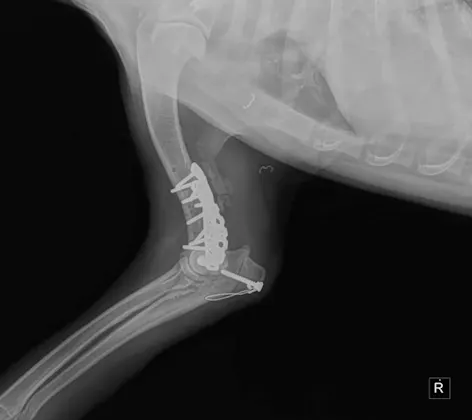

Orthopedic Surgery

Orthopedic surgery can help pets who suffer from joint problems, torn ligaments, broken bones, and even help correct congenital problems.

Bone Plating

Bone plating is one of the strongest and most effective methods of fixing a fracture. Fractures are common in pets and are caused by a variety of reasons.